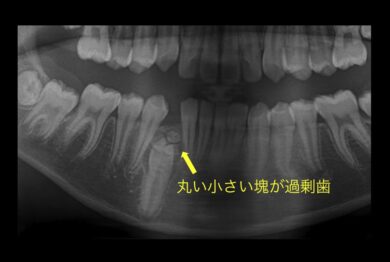

小学生のお子様の症例です。乳歯が抜けても永久歯が生えて来ないことを主訴に来院されました。

レントゲンを撮影したところ、過剰歯(余分な歯)のせいで永久歯が萌出できない事が判明したため、過剰歯を取り除き引っ張り出す処置を行うことにしました。